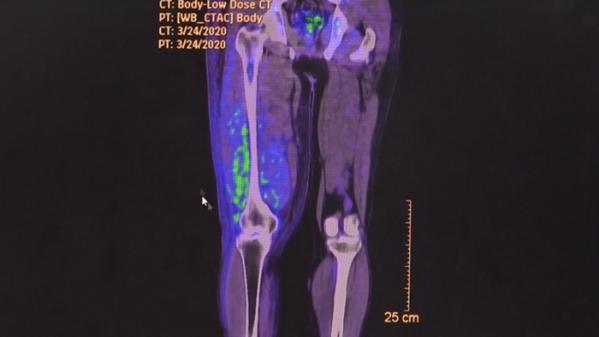

과학고에 재직 중인 박성철 씨(가명)는 올해 3월 육종 진단을 받았다. 육종, 즉 뼈나 연부 조직에 발생하는 이 종양은 10만 명당 1~2명 발생하는 매우 희귀한 질환이다. 그런데, 같은 학교에 재직하던 선생님이 이 희귀한 암에 걸려 사망하고 심지어 타 학교의 선생님 역시 육종 판정을 받았다는 소식이 들렸다. 이들의 공통점은 바로, 교육 목적으로 3D 프린터를 장시간 사용했다는 것이다.

산업안전보건연구원 실험 결과, 3D 프린터의 소재로 쓰이는 합성수지 필라멘트가 가열되는 과정에서 암을 유발하는 유해물질이 다량 검출되었다. 필라멘트가 녹으면서 발암물질이 공기 중에 퍼지고, 이 물질에 장시간 노출될 경우 건강 영향이 있을 수 있다는 연구 결과였다. 박성철 씨는 본인의 건강보다도 함께 3D프린터를 사용한 학생들의 건강이 걱정된다고 말한다. 교육의 현장인 학교, 가장 안전해야 할 공간이 발암물질과 생식독성작용물질로 위협받고 있었던 것이다.